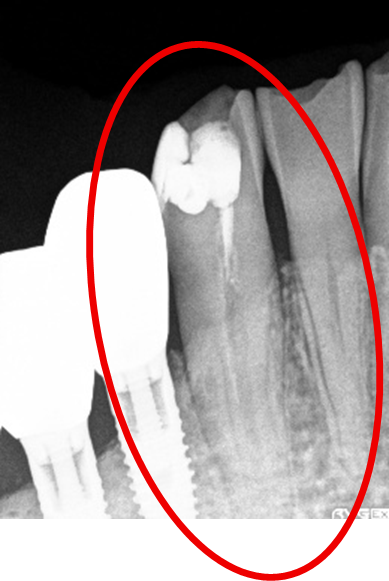

女性Mさん 40代(オールセラミック冠)

主訴

上の前歯が欠けた。

治療内容

神経をとる治療をし、根管治療後、ファイバーコアを入れ、オールセラミック冠を被せました。

所感

右前歯がむし歯で大きくかけていました。レントゲンを撮り詳しく診てみると、むし歯が深く、神経をとる治療が必要なことがわかりました。被せ物は、メタルフリーの治療を希望されましたので、ファイバーコアを入れオールセラミック冠を被せました。右上にむし歯があります。今後、そこの部分に取り組んでいきます。

オールセラミック冠1本:¥104,500(税込)

Before

むし歯が深く、神経に到達するむし歯でしたので、根管治療をしました。

After

根管治療終了後